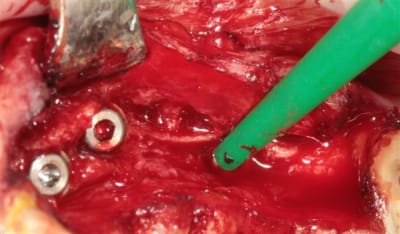

OK nous n'y sommes pas encore, mais je me suis fais une petite intervention sympa ce matin, avec un nouvel outil (qui n'est pas sur les photos ....because chut!) qui devrait permettre de simplifier la pratique de l'expansion, afin que tout un chacun puisse pratiquer ce sport sympa, et si tout va bien je pourrais vous en parler (peut être) en Juin.

crête en lame d'1 mm..pour 23/24/26

Axioms 3.4 x10 (2) et 3.4x 8

Mais, ce post est surtout provoqué car j'ai utilisé un nouvel outil pour l'expansion et si la suite le confirme, les ostéotomes "classiques" pourraient bien êtres renvoyés sur l’étagère des outils du souvenir..

une crête sympa, 3 implants + rog?